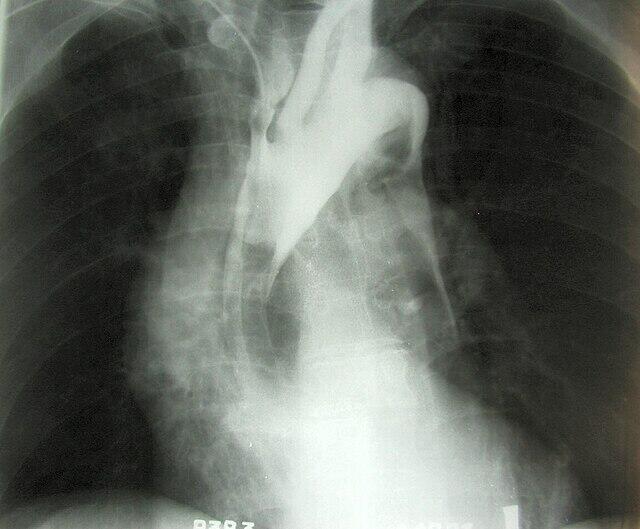

Ohle: The aorta is our largest, highest-pressure artery and runs the entire length of the chest and abdomen. An aneurysm is a weakening in the wall of this vessel, which can balloon and rupture. Aortic aneurysms can also exist without doing any serious harm. An aortic dissection is a bad thing happening right now. It happens when a tear or weakening in the inner layer of the aorta “unzips” the vessel. At a prehospital level, it doesn’t really matter whether this giant hose of life is bursting or tearing. They’re both true, surgical emergencies.